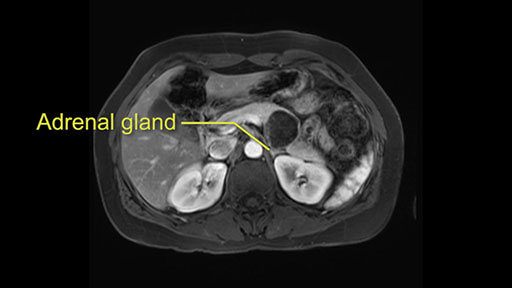

The lesion also is quite posterior. While the plane between the cyst and the left adrenal gland is often preserved, we do have to pay attention here so that we remain in the right plane and maintain our margin here. Occasionally in these cases, en bloc adrenalectomy needs to be performed.

Sometimes with even benign lesions of the spleen you can have quite a lot of inflammation in the retroperitoneum and so I do think about and wonder whether I will have some difficulty in the retroperitoneum and I usually look at the scan for that purpose. It looks like there is no inflammation in the retroperitoneum. It does look very close to the patient’s left adrenal gland but knowing the planes and suspecting that there isn’t any active inflammation, this should be able to come off the left adrenal gland without any difficulty. But obviously prepared to take some of the left adrenal if that’s necessary in this procedure. So those are my procedure-specific slowing down moments in a distal pancreatectomy when I’m considering a laparoscopic approach. I think the patient-specific slowing down moments in this particular case I have discussed with the procedure-specific moments. I don’t really see any other issue or that I have to be careful of or consider.

So first, I'll show you the scan. Here's the traditional view, where you see the cyst, which is in the body of the pancreas. And you see over here, it's got a quite thick wall. And going a little bit back also, here you see a septation which is very important, because I think a septation is what separates this from, for instance, the pseudocyst of the pancreatitis. And also the location of the cyst you see here, abutting the adrenal gland and going down a bit more, it's also quite close to a bowel loop. So when thinking about this cyst: female, the location in the body of the pancreas, thick wall, septation, and as you can read in history, it was basically asymptomatic, so no signs of pancreatitis. So, this probably all points towards a mucinous cystic neoplasm.

So what I would normally do in these patients, I would look at the abutment of any other organs, one, which is here, potentially the adrenal gland and two the small bowel. And two, look at the distance from the vessels which I would normally do in a coronal view. So you can easily measure the distance and third I look at the insertion of the inferior mesenteric vein. Now we can probably also see that on here. Although it's better on a CT scan and it's better on a coronal view, you want to know where the inferior mesenteric vein comes into either the splenic or the SMV, because that is typically a very important slow down moment when you mobilize the lower portion of the pancreas knowing where the inferior mesenteric vein comes in either the splenic vein or the SMV. So those are I think the three most important points for the CT scan.

After you've slung the pancreas, to the left of the cyst, and if you encounter any adrenal involvement later after you have transected the pancreas and you move to the left side of the patient towards the spleen, take either the entire or partial left adrenal gland with the resection. If you go underneath the adrenal gland, and it's probably best to do a full RAMPS (Radical Antegrade Modular Pancreatosplenectomy) procedure, that is where you take the Gerota’s fascia completely onto the mucinous cyst. And that's very crucial to get a radical resection if you think the adrenal gland is involved.